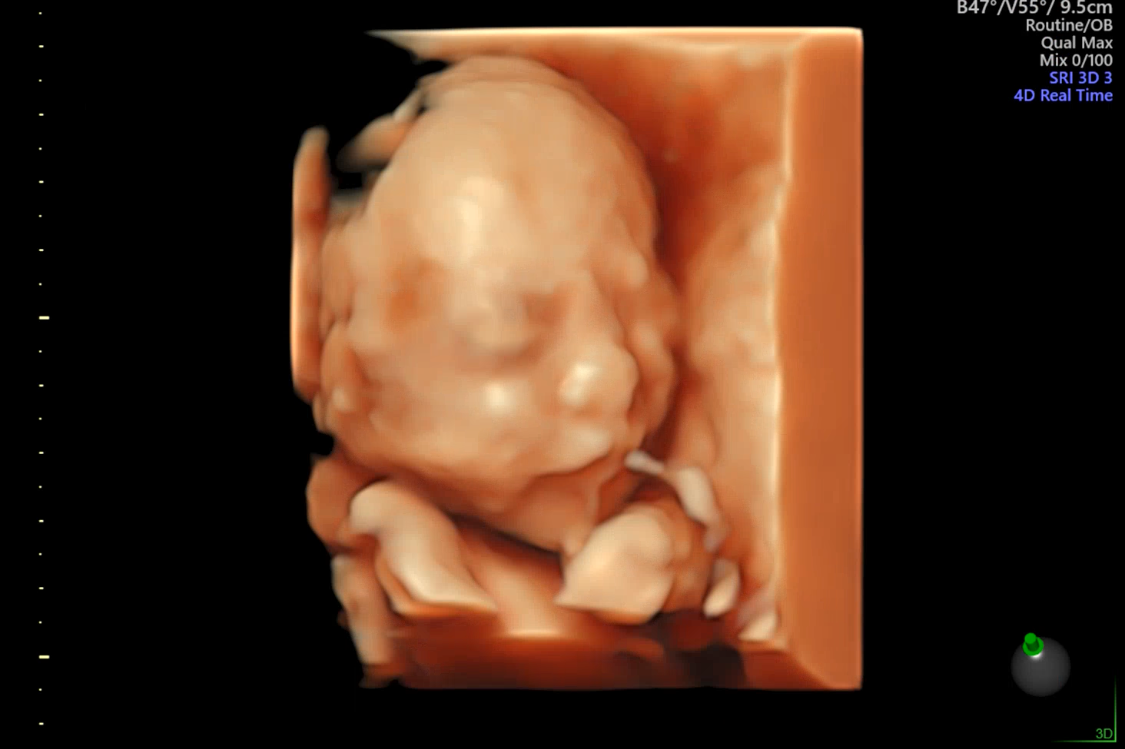

2. 정밀초음파 (손, 발, 귀, 얼굴)

손가락, 발가락, 귀, 얼굴 등등은 별도로 다른방에서 따로 봐주셨다!

그래도 샘이 입체초음파까지 동원해서 잘 잡아주셨다.

울 아가 얼굴 사진도 한장 찍어주심❣❣❣

오늘 처음 재대로 보는 울아가 얼굴..

생각보다 이쁘다 귀여워!

샘이 아직은 희미하게 나온다며

28주에 따로 보는걸로 잘 보라시더라구.